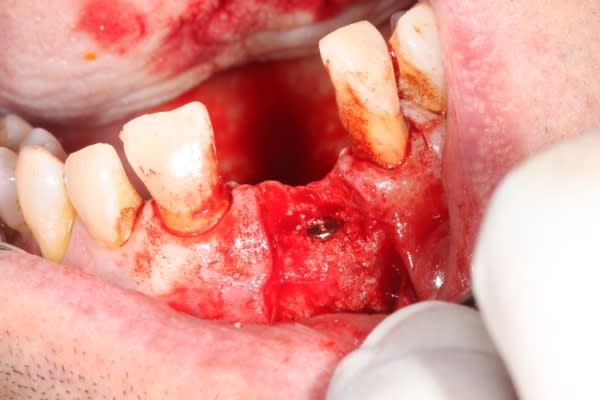

Extraction implantation immédiate mais il y a au moins 7 spires à nue... (photo 1, 2)

dans cette technique un pilier de 2mm de haut est vissé sur l'implant, ce pilier contient un orifice qui permet de transfixer la barre (photo 3,4)

l'espace créé est rempli avec un biomat et le tout est recouvert d'une membrane